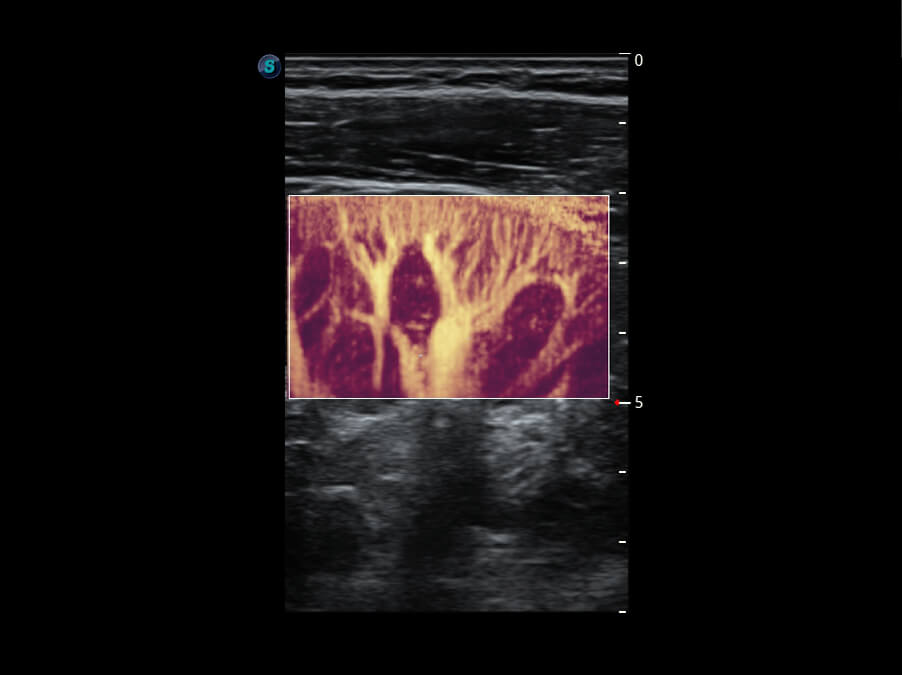

超宽频带技术,为容积成像带来优质的二维图像基础,为您呈现丰富的结构细节,栩栩如生地展示宝宝的宫内形态以及各种组织的立体结构。